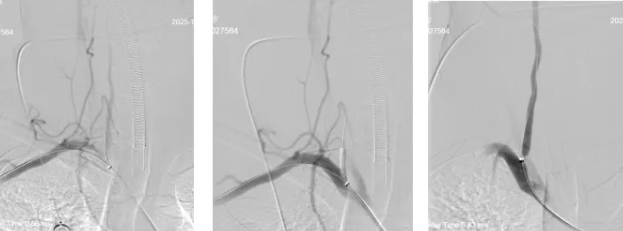

为最大程度抢救脑细胞,缩短脑组织供血恢复间隔,神经内三科卒中救治团队立即启动绿色通道实施介入取栓治疗,麻醉医师迅速抵达导管室,神经内三科主任席聪对患者进行急诊血管造影后发现:患者左椎动脉起始段闭塞,右椎动脉起始部次全闭塞。

时间就是大脑!在与病人家属充分沟通后,神经内三科介入团队对患者进行了全麻下:颅内动脉取栓术+颅内动脉球囊扩张+椎动脉扩张+椎动脉支架植入术。

术中,介入团队精准定位血管闭塞部位,通过微导丝“探路”联合球囊扩张技术开通右侧椎动脉开口,造影椎开口残余狭窄60%。基底动脉血栓形成,基底动脉管腔狭窄55%,基底动脉尖堵塞,右侧大脑后动脉及小脑上动脉未见显影,左侧大脑后动脉P3以远闭塞。

席聪准确锁定患者基底动脉处血栓,采用抽吸取栓技术快速开通血管,成功取出堵塞部位2cm的血栓。再次造影示:右侧大脑后及双侧小脑上动脉再通,右侧大脑后动脉P3段以远闭塞,考虑慢性闭塞,推注替罗非班,血流明显加快。随后采用支架植入术开通右侧椎动脉开口处,术中影像显示:支架贴壁良好,无明显残余狭窄,颅内血管显影良好。